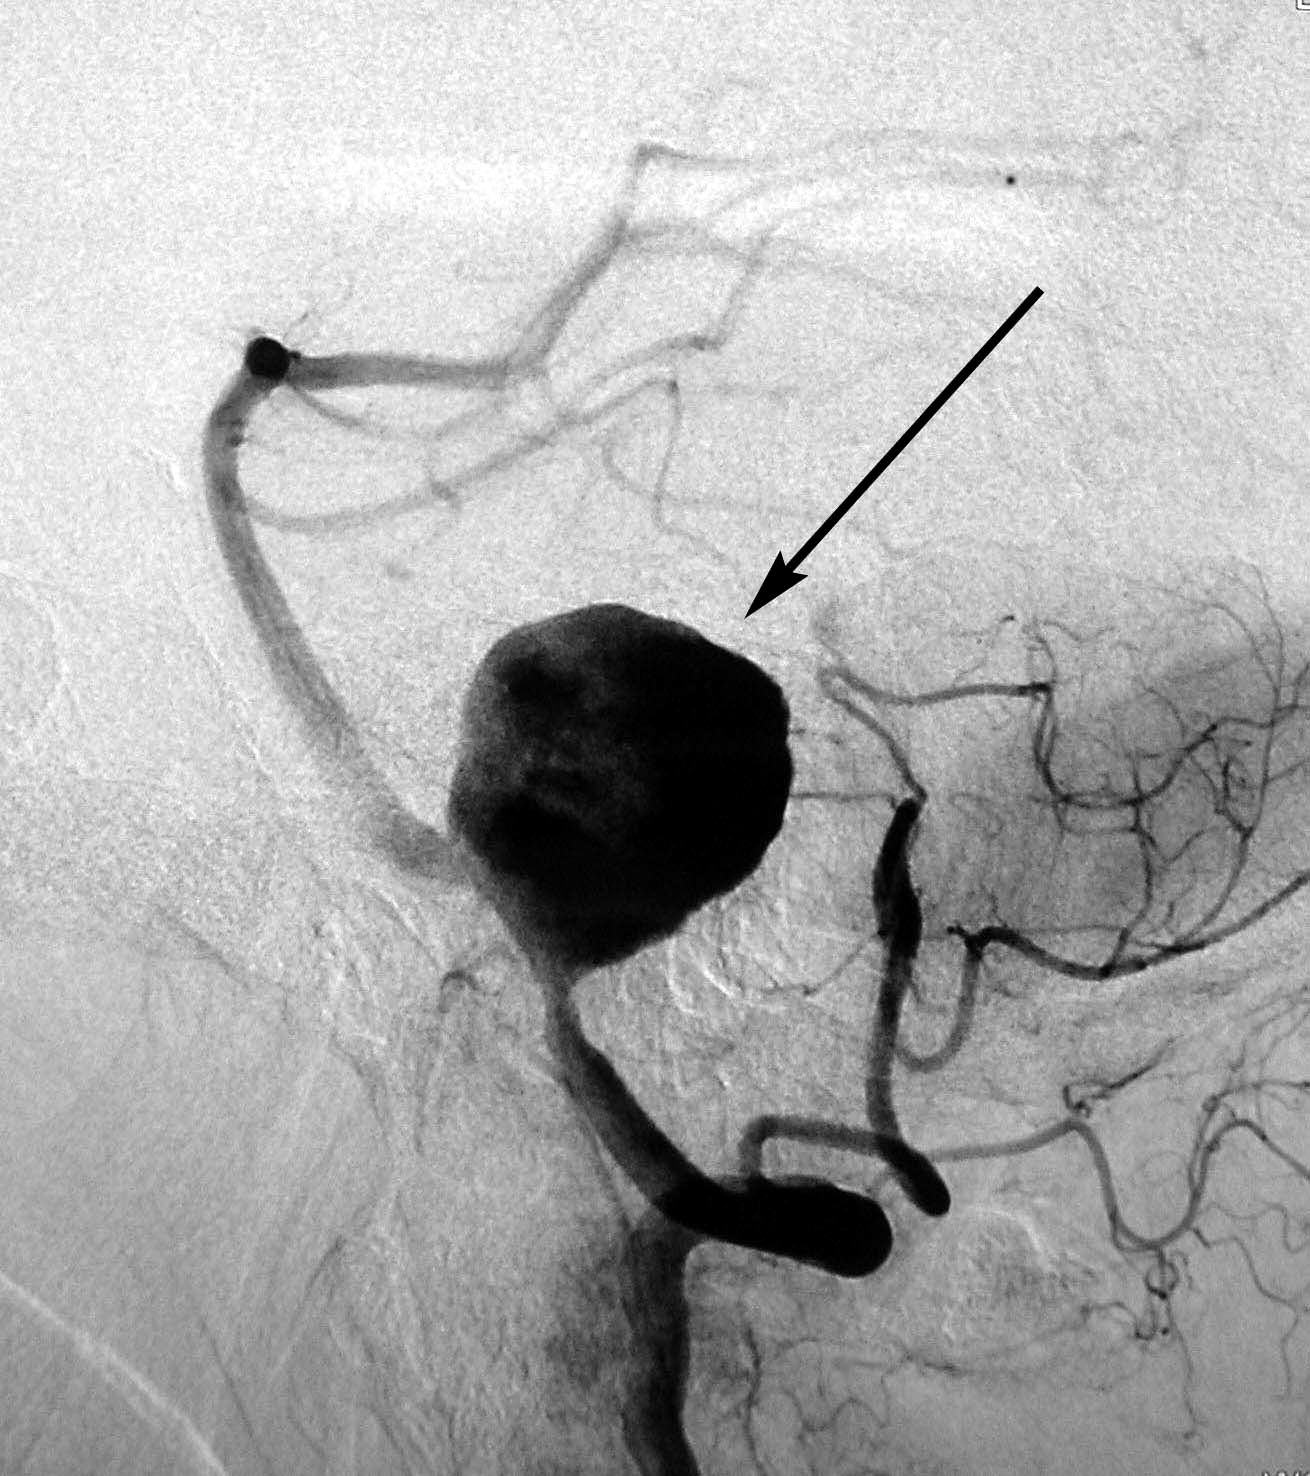

Снимки и иллюстрации микроаневризм сосудов головного мозга